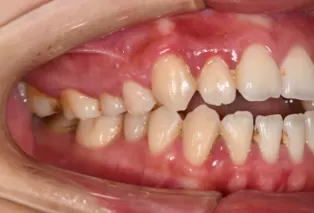

Photos intra-orales